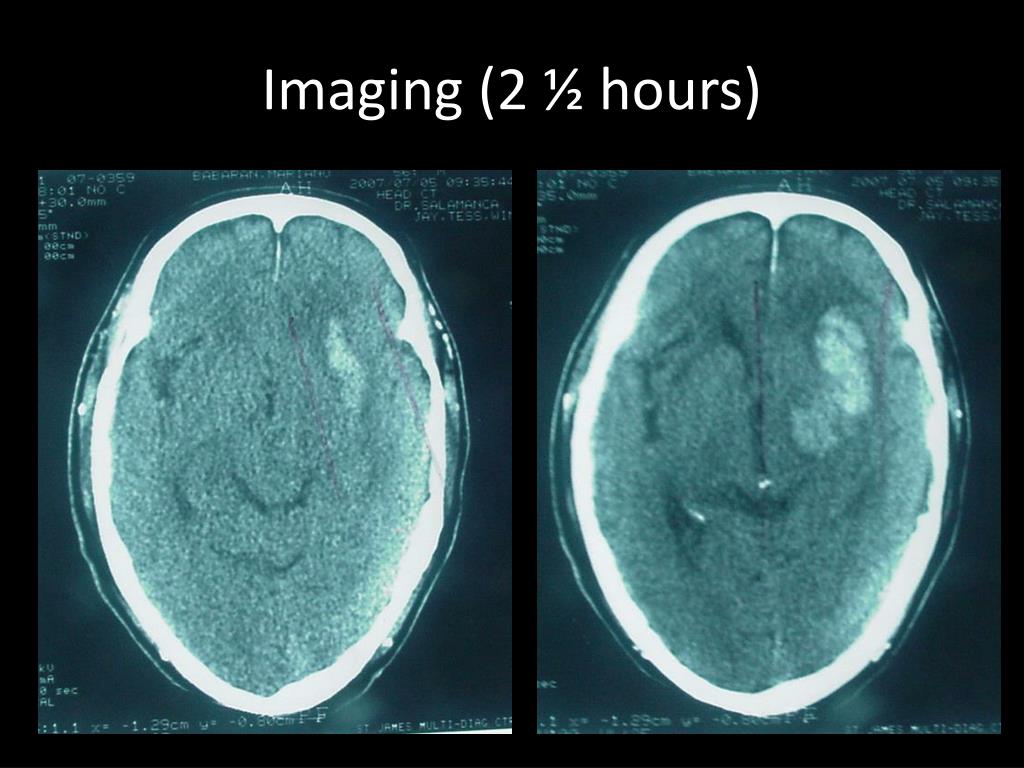

6. Imaging ( 2 ½ hours)

7. Imaging (2 ½ hours)

8. Imaging (2 ½ hours)

9. Imaging (2 ½ hours)

10. Imaging (2 ½ hours) • Intracerebral hematoma with an estimated volume of 30cc in the L capsuloganglionic region. • With perilesional edema, mass effect and midline shift • No IVE, HCP